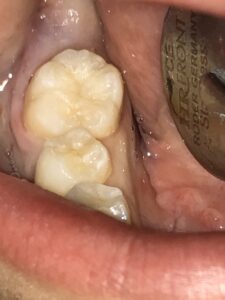

神経を保護するMTAセメントを敷いた後、ダイレクトボンディングで最終修復を行いました。

ほとんど元通りに修復することができました(とは言っても人工物です…)